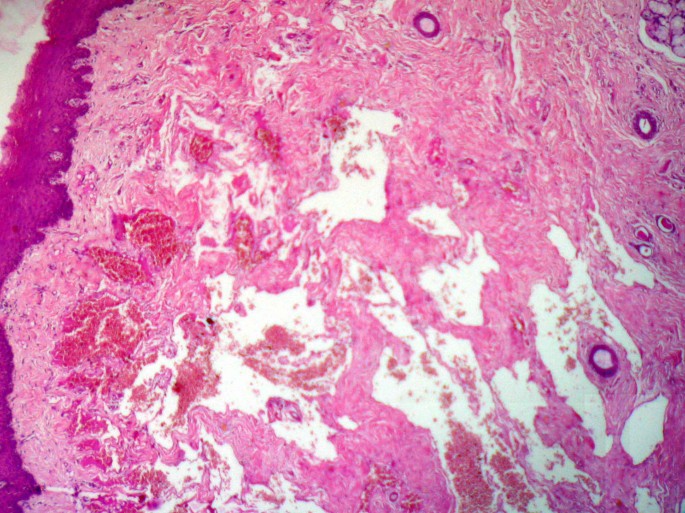

Routine microscopy showed predominantly entrapped ducts and effaced acini amid proliferating thin walled endothelium lined cavernous type of blood vessels (Fig 1 & Fig 2A,B,C &2D). In other fields, displacement of mucous salivary acini and ducts towards the surface epithelium was evident. The intervening connective tissue between the surface epithelium and the main body of the lesion lacked lesional tissue but showed survival of ducts and dense collagenization. (Fig 3). After ascertaining that the lesion was not associated with any syndrome, it was coded as hemanigoma involving minor salivary glands.

The microscopic features of salivary gland hemangioma is distinctive, and is characterized by effaced acinar structures, retained ducts, and lesional tissue within the confines of salivary gland lobules [1]. Although these histologic features are regarded as diagnostic of primary hemangioma in major salivary glands, it cannot be said of minor salivary glands. This is in part because of lack of encapsulation in minor salivary glands, and thus assessment of origin within the salivary gland connective tissue stroma is rendered more difficult.

In the present case, the presence of vascular proliferations in the main substance of the salivary gland associated with retained ducts and effaced acinar units may indicate intraglandular origin, as it is at a deeper location than one would expect. But in the absence of any specific histological parameters to assess minor salivary gland origin with certainty, it is virtually impossible to exclude secondary involvement [7].